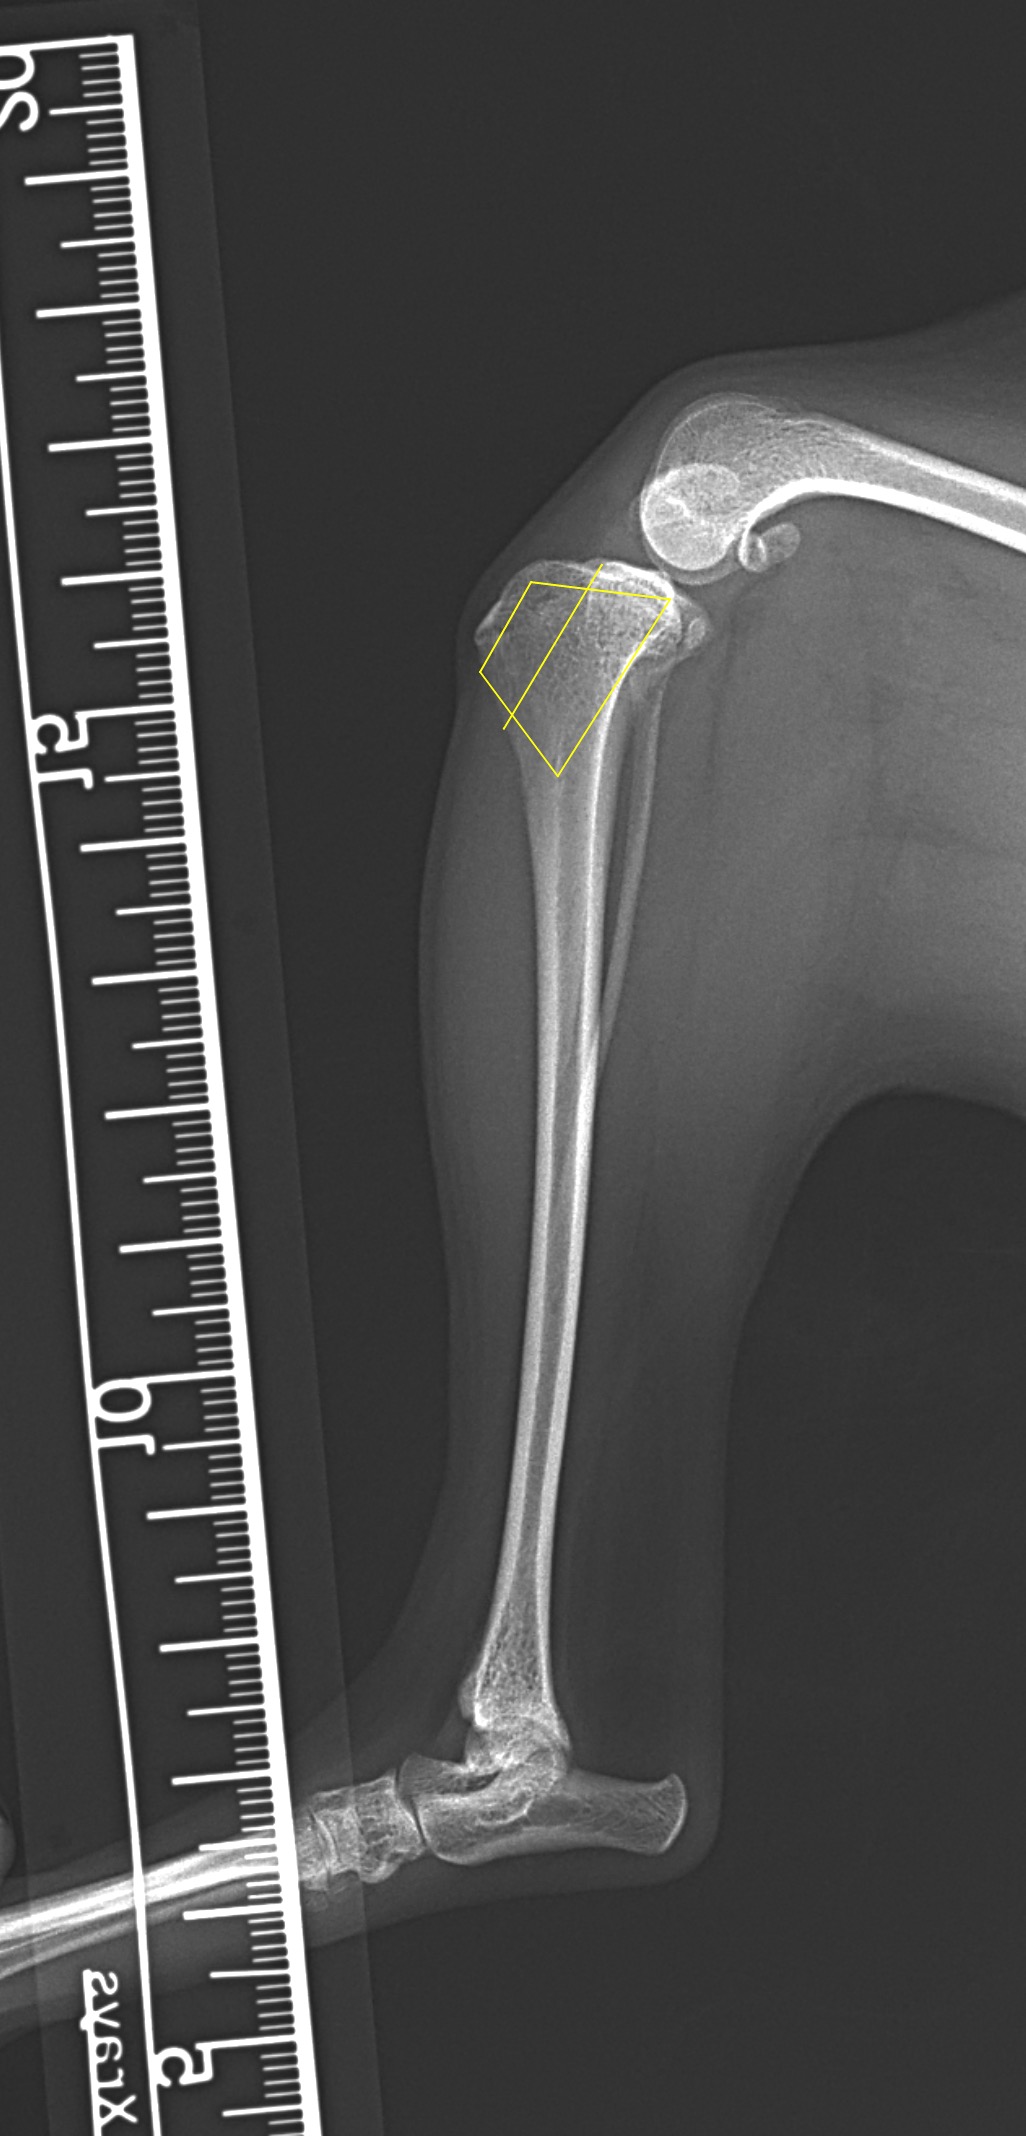

膝蓋骨内方脱臼 グレード4

小型犬の膝蓋骨内方脱臼(MPLグレード4)に対する整復依頼があった。徒手によって膝蓋骨が大腿骨滑車内に完納しない、つまり重症である。BRTにより大腿骨滑車形成術を行い、内側広筋の筋膜リリース、パテラを滑車に戻した状態で余剰関節包の再建術を実施。脛骨粗面を骨切り、大腿四頭筋〜膝蓋骨〜脛骨粗面〜足根関節のアライメント調整を行い仮固定ピンによりT.T.Tの移動幅を決定。5.0mmのスパイク形状のスペーサーでLateralizationを行った。1.5 Staggered Locking Patella Plate for T.T.Tを利用し、強固に粗面の固定術を実施。最後に骨切り部位にBRTで得られた海綿骨を移植し終了。日本ではまだ馴染みの少ない術式ではあるが、ドイツを中心にヨーロッパにおいて認知されはじめている。